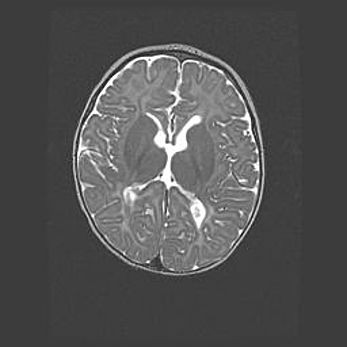

Ниже представлена  галерея МРТ снимков, полученных с применением LMT неонатальных матричных РЧ катушек. Также каждая группа МРТ снимков сопровождается информацией о пациенте (диагноз, возраст, вес, пол, срок гестации) и краткой сопроводительной расшифровкой диагноза.

Церебральная ишемия II.

Возраст: 5 дней

Вес: 3400 г

Пол: женский

Окружность головы: 35 см

Срок гестации: 39 недель

Церебральная ишемия – это заболевание, характеризующееся недостаточностью (гипоксией) либо полным прекращением (аноксией) снабжения мозга кислородом по причине закупорки одного или нескольких сосудов. Это приводит к  что метаболическим расстройствам различной степени тяжести в тканях головного мозга, развитию коагуляционных некрозов и гибели нейронов.